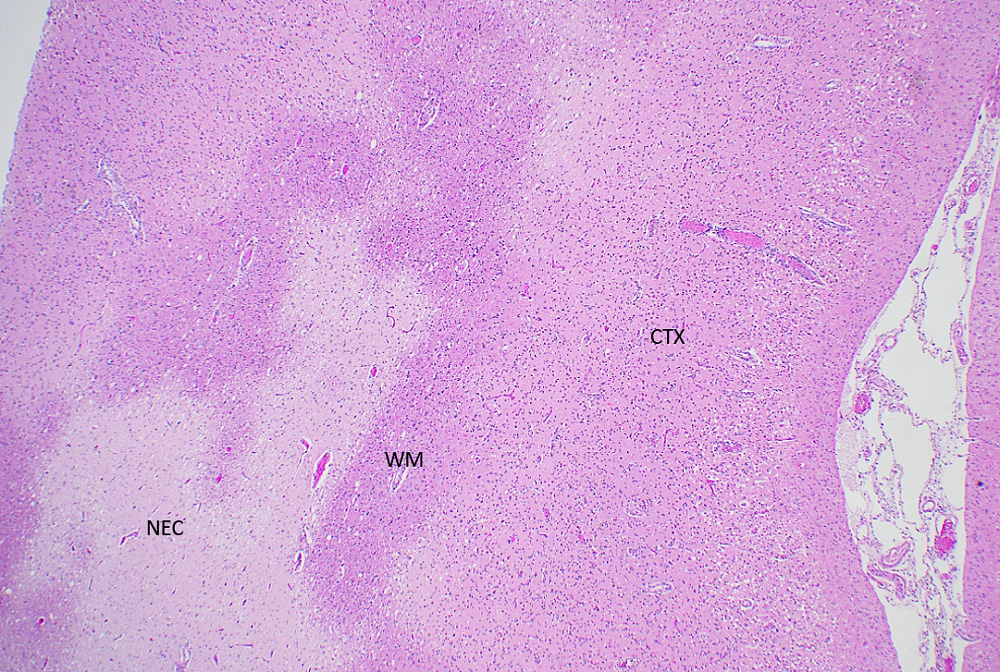

Microscopic (histologic) description

- Acute infarct (1 - 4 days) (Histopathology 2011;58:333)

- Neuronal changes: hypereosinophilic perikaryon (red dead neurons), cell body shrinkage, pyknosis (i.e., nuclear hyperchromasia), loss of demarcation of the nuclear features in later phases

- Neuropil vacuolation (i.e., tissue edema)

- Pannecrosis: all cell populations (i.e., neurons, glia, blood vessels) are necrotic; dead cells remain visible as hypereosinophilic structures that preserve the cell and nuclear outlines (pale neurons or "ghosts")

- Geographic necrosis: liquefied necrotic tissue is well demarcated from the adjacent viable tissue

- Subacute (5 - 14 days)

- Dense macrophage infiltration and scattered siderophages

- Variable neutrophilic infiltration

- Peripheral reactive astrocytosis and microglial activation (i.e., rod shaped microglia)

- Hypereosinophilic neurons are still present in gray matter

- Neovascularization of necrotic tissue and reactive endothelial cells

- Chronic (15 days - years)

- Cavitated lesion with vessels and macrophages surrounded by a glial scar

- Reactive astrocytes in the edge of the cavitation